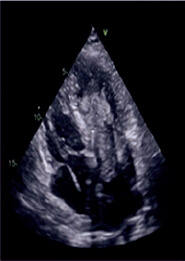

A su llegada al laboratorio de hemodinámica el paciente persistía en situación de shock cardiogénico y además presentaba bloqueo auriculoventricular completo. Se implantó de forma emergente por vía venosa femoral derecha un marcapasos temporal y la por arteria femoral izquierda se implantó un dispositivo Impella CP (AbioMed, Danvers, Massachusetts, Estados Unidos). Por acceso femoral derecho se realizó la coronariografía, que mostró oclusión aguda de aspecto embólico en la circunfleja media y la coronaria derecha distal (figura 1A, B). Se realizó tromboaspiración en ambas arterias y se obtuvo abundante material trombótico. Se llevó a cabo una angioplastia simple en la coronaria derecha distal, con un restablecimiento subóptimo del flujo epicárdico (Thrombolysis in Myocardial Infarction ≤ 2) (figura 1C, D). Tras el intervencionismo se realizó ecocardiografía transtorácica que mostró la presencia de una masa intracavitaria adherida al techo de la aurícula izquierda con extensión al ventrículo izquierdo (figura 2). Ante estas imágenes y la inestabilidad hemodinámica persistente a pesar de los fármacos vasoactivos a dosis máximas y el soporte circulatorio percutáneo, se contactó con el equipo de cirugía cardiaca y se decidió implantar un oxigenador extracorpóreo de membrana de forma percutánea y retirar el Impella CP.

Figura 2. Masa desplazada al ventrículo izquierdo.

Previamente a su ingreso en la unidad de cuidados intensivos cardiológicos se realizó un escáner cerebral en el que se observó una oclusión completa de diferentes arterias intracraneales y edema cerebral difuso. Durante su estancia en la unidad de cuidados intensivos cardiológicos persistió en situación de shock cardiogénico refractario; se realizó una nueva ecocardiografía transtorácica en la que se observó una tumoración en la aurícula izquierda que condicionaba una doble lesión (insuficiencia y estenosis) mitral grave y disfunción grave del ventrículo izquierdo.